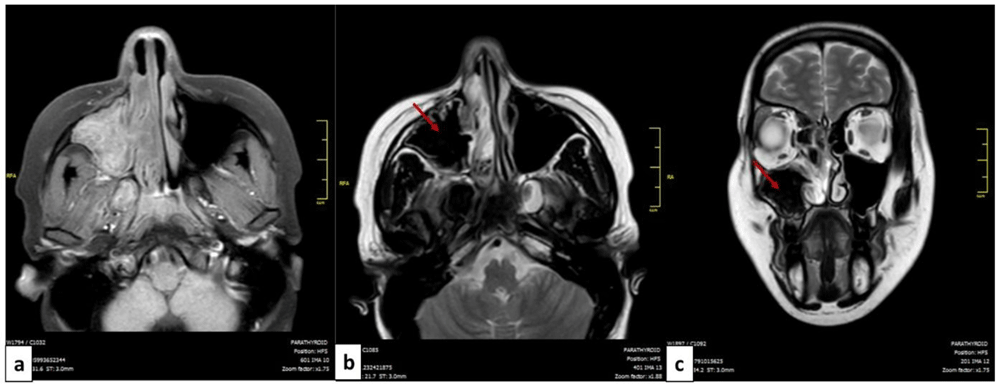

MRI of the facial mass was performed in four patients. In all cases, it showed T2 hypointense (signal void) images suggestive of the mycotic origin (Figure 2).

MRI of the facial mass of a patient with allergic fungal rhinosinusitis: axial cut (a,b) and coronal cut (c). The filling of the left maxillary sinus is presented in isosignal T1 (a) and in hyposignal T2 or signal void (red arrow) (b,c).

The computed tomodensitometry scan images contribute to the diagnosis. In the case of fungal balls, the affection mostly concerns the maxillary sinus. The most reported features were calcifications within the maxillary sinus followed by complete opacification, partial opacification with an irregular surface and bony sclerosis or bone thickening11. These signs remain nonspecific and could be seen in sinusitis of other origins or neoplasms. The MRI is more performant, the fungal ball is hypointense on T1-weighted and T2-weighted images. In the case of allergic FR, scan images typically show bilateral pansinusitis. The opacification of the sinuses is explained by the hyperattenuated mucin. In many cases, as noted for our patients, expansion and thinning of sinus walls were reported. T1-weighted MRI images may show mixed signal intensities. T2-weighted images are mostly hypointense but may show flow voids1.